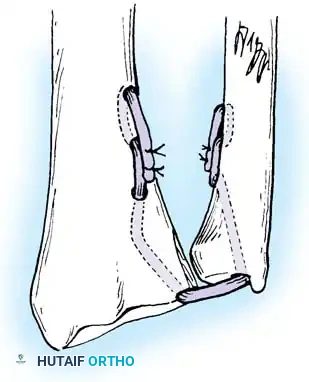

In chronic settings where the TFCC is irreparable, anatomic ligament reconstruction using a tendon autograft (e.g., palmaris longus) is indicated. The graft is routed through the distal radius and ulnar fovea to recreate the dorsal and volar radioulnar ligaments.

Tendon graft routing through osseous tunnels in the radius and ulna for anatomic reconstruction of the DRUJ ligaments.